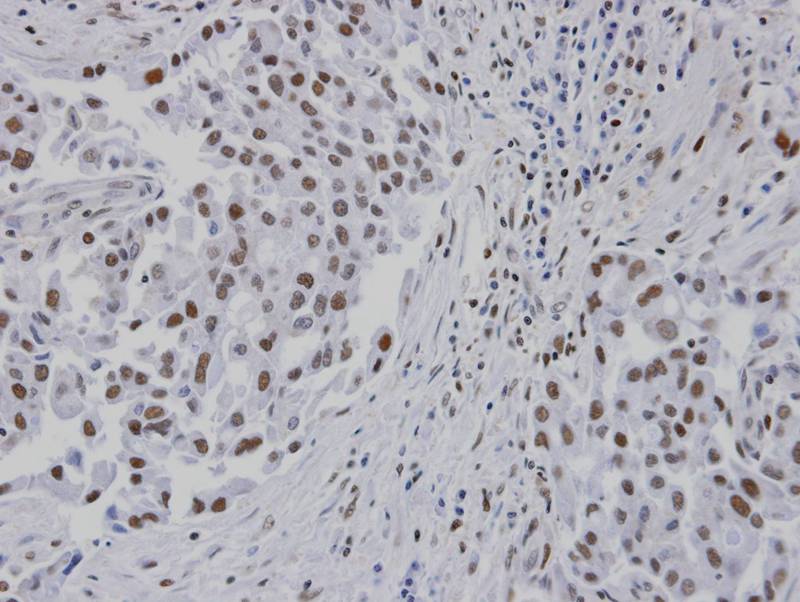

Immunohistochemical analysis of paraffin-embedded lung CA patient tumor, using RPA 14 kDa subunit antibody at 1: 100 dilution.